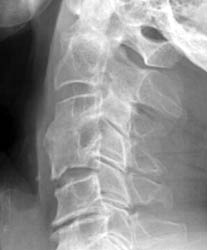

Conservative management utilizing a rigid cervical collar was prescribed for 6

months. 5 months later bony healing has

occurred with incorporation of the graft.